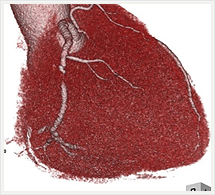

画像紹介

CTでは輪切り像の他にも立体的な画像(3D画像)を作成することもできます。そのためにはより細かくキレイな画像を撮影しなければなりません。当院では64列CTを導入しており、キレイな画像をより細かく撮影することができます。その画像を元に3D画像を作成することによって、より正確な手術のシミュレーションが可能になります。実際に手術をしたときの様子が、手術をする前に画像として見らます。外科系の手術には欠かせない技術となっておりますが、内科系でも血管内手術にも多く利用されております。

当診療放射線技術科では毎日各診療科に対して、その手術に最適な3D画像を提供しております。

以下にその3D画像を一部分紹介します。

心臓

腹部・腹部血管

門脈(黄)